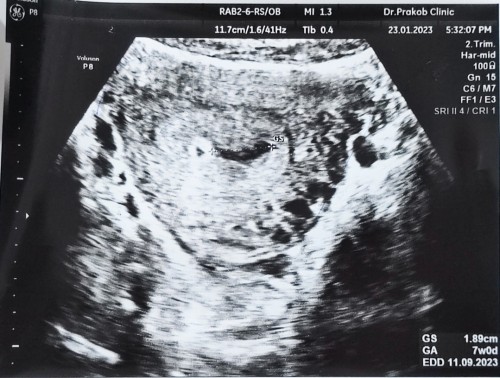

อัลตร้าซาวด์ 7 สัปดาห์ไม่เจอตัวน้อง

วันนี้ไปอัลตร้าซาวด์ผ่านหน้าท้องอายุครรภ์ 7 สัปดาห์อัลตร้าซาวด์เจอแต่ถุงการตั้งครรภ์ค่ะคุณหมอบอกมีสิทธิ์ที่จะท้องลม มีแม่ๆคนไหนตั้งครรภ์ 7 สัปดาห์แล้วยังไม่เจอตัวน้องบ้างคะกังวลมากค่ะกลัวจะท้องลม😭

เหมือนเห็นถุงไข่แดงอยู่นะคะแม่ อายุครรภ์ ยังน้อยต้องซาวช่องคลอดค่ะถึงจะเจอตัวน้องไม่ต้องกัววลนะคะ หมอนัดอีกรอบ เจอน้องแน่นอนค่ะ

บ้านนี้ก็7สัปดาห์ค่ะ เจอแต่ถุงการตั้งครรภ์ค่ะ อีก2อาทิตย์หมอนัด พอซาวอีกก็ไม่เจอค่ะ ใช้กล้องส่องภายในถึงจะเจอถุงไข่แดง

อายุครรภ์น้อยต้องซาวช่องคลอดถึงจะเห็นชัดค่ะ บ้านนี้หมอต้องซาวทางช่องคลอดถึงจะเจอ